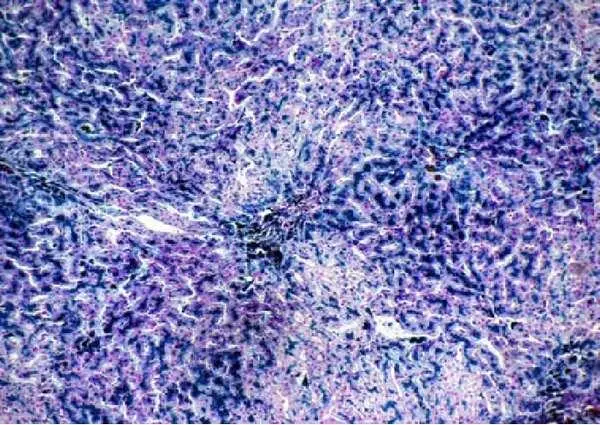

Рисунок 20 – Гемосидероз печени при врожденном гемохроматозе. Окраска на железо по Перлсу. Х200